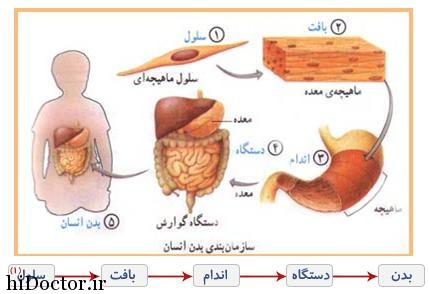

عکس داخل شکم انسان. در این همان طور که مشخص است شکم حالت بیضی شکل پیداکرده و این بیضی که کناره های شکم کشیده شده است. تعداد سلول های بدن انسان حدود ۳۷ ۲ تریلیون تخمین زده شده اند. Abdomen که در زبان عامه به غلط به آن دل نیز می گویند در آناتومی به قسمتی از تنه گفته می شود که مابین دیافراگم از بالا و سطح فوقانی لگن خاصره از پایین قرار دارد. ربات دیدنی ربات انساننمای چینی به صورت یک دختر جوان ساخته شده و جیا جیا نامگذاری شده است این ربات طوری برنامهریزی شده که میتواند صحبت کند و احساسات خود را از طریق تغییرات در چهره حالات.

رونمایی از جرد لتو در نقش جوکر عکس. این تصاویر عجیب و بی نظیری كه مشاهده می کنید مربوط به یك ساختمان واقع در كشور هلند است كه شبیه انسان ساخته شده و از تاریخ چهاردهم مارس 2008 برای بازدیدكنندگان فعال بوده است. فرم شکم زنان باردار دختر. هر قسمت بدن از انواع مختلف سلول تشکیل شده است.